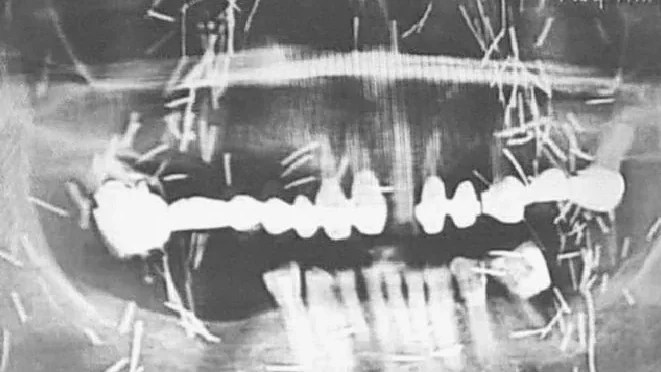

Traditionally involving charms or spiritually empowered objects like needles or pieces of precious metals, susuk was historically associated with performers, dancers, aristocrats, and individuals seeking influence.